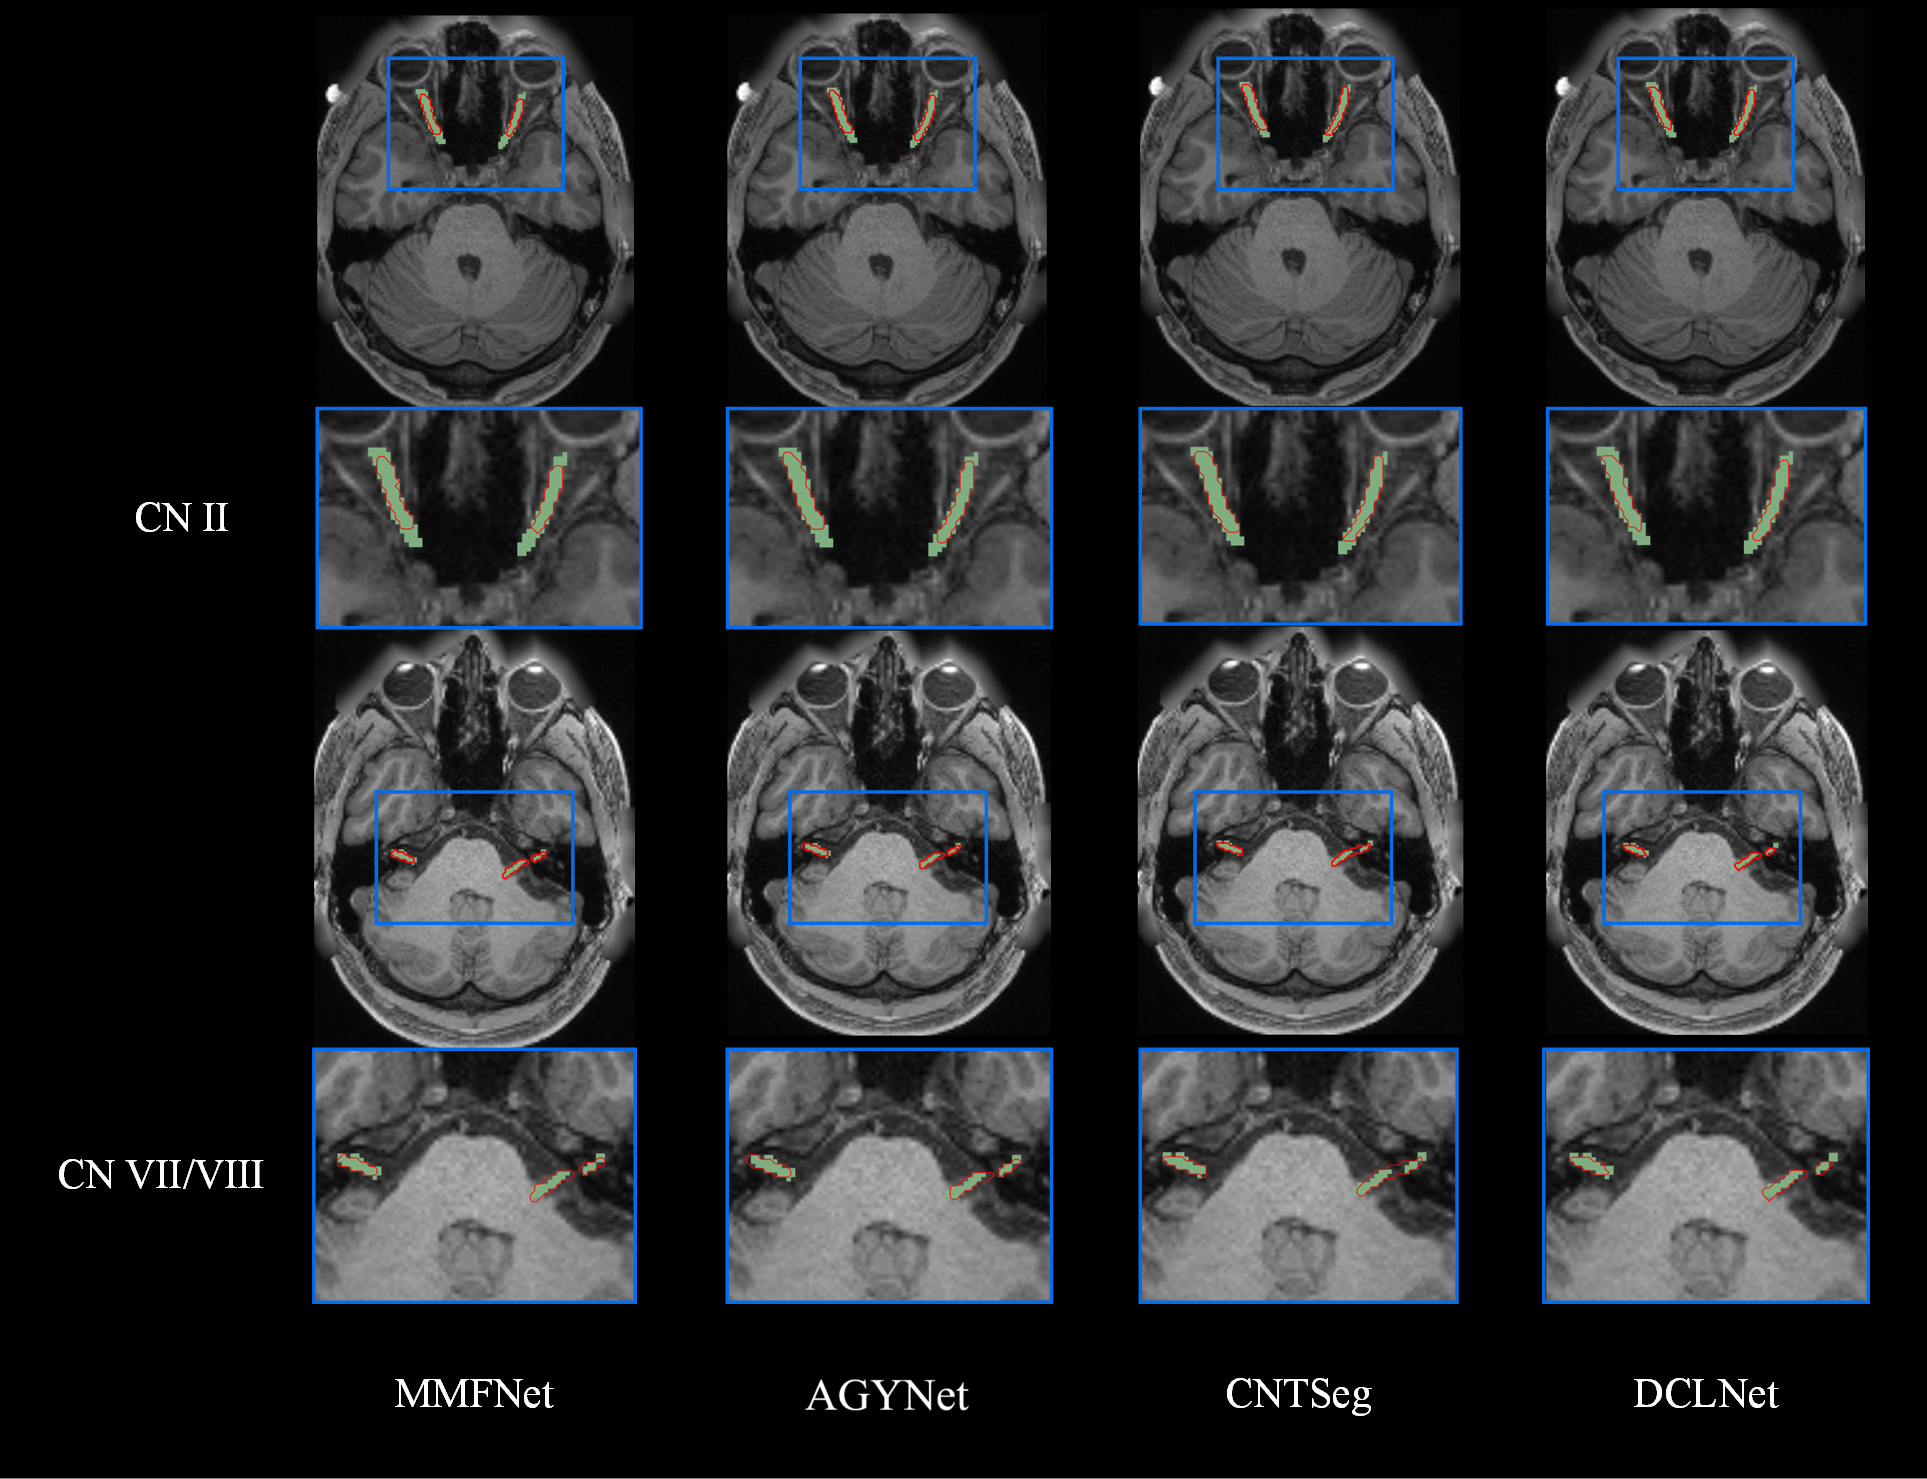

This figure shows qualitative results of DCLNet.

To provide a more intuitive illustration of the performance of our method, we select subject No. 100206 from the HCP dataset to represent the CNs parcellation results. Figure 2 shows the qualitative CN II and CN VII/VIII parcellation results generated by different methods. The green areas in the figure represent expert annotations, while the red areas correspond to the predictions of each method. As shown in Figure 2, our method demonstrates greater overlap with the ground truth compared to other SOTA methods. Notably, it achieves superior accuracy in detecting regions near anatomical boundaries and in cases where the labels are non-contiguous. For instance, the CN VII/VIII prediction results from the AGYNet and CNTSeg show that, under discontinuous labeling conditions, a large number of incorrect samples are falsely identified as positive. This highlights the robustness of our method in handling fine anatomical structures.